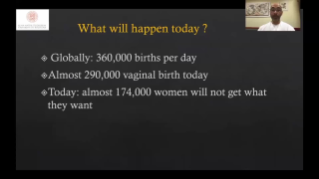

? necessĂĄrio otimizar fluxos de trabalho de obstetrĂcia e ginecologia para suportar grandes volumes na triagem da saĂșde da mulher. Por exemplo, as mĂĄs-forma??es do sistema nervoso central (SNC) s?o uma das anomalias congĂȘnitas mais comuns. Obten??o de imagens ruins devido Ă mĂĄ posi??o fetal, o MSP Ă© particularmente difĂcil de ser encontrado em um ultrassom 2D. Portanto, a detec??o e as medi??es automĂĄticas podem aumentar muito a eficiĂȘncia da realiza??o do exame.